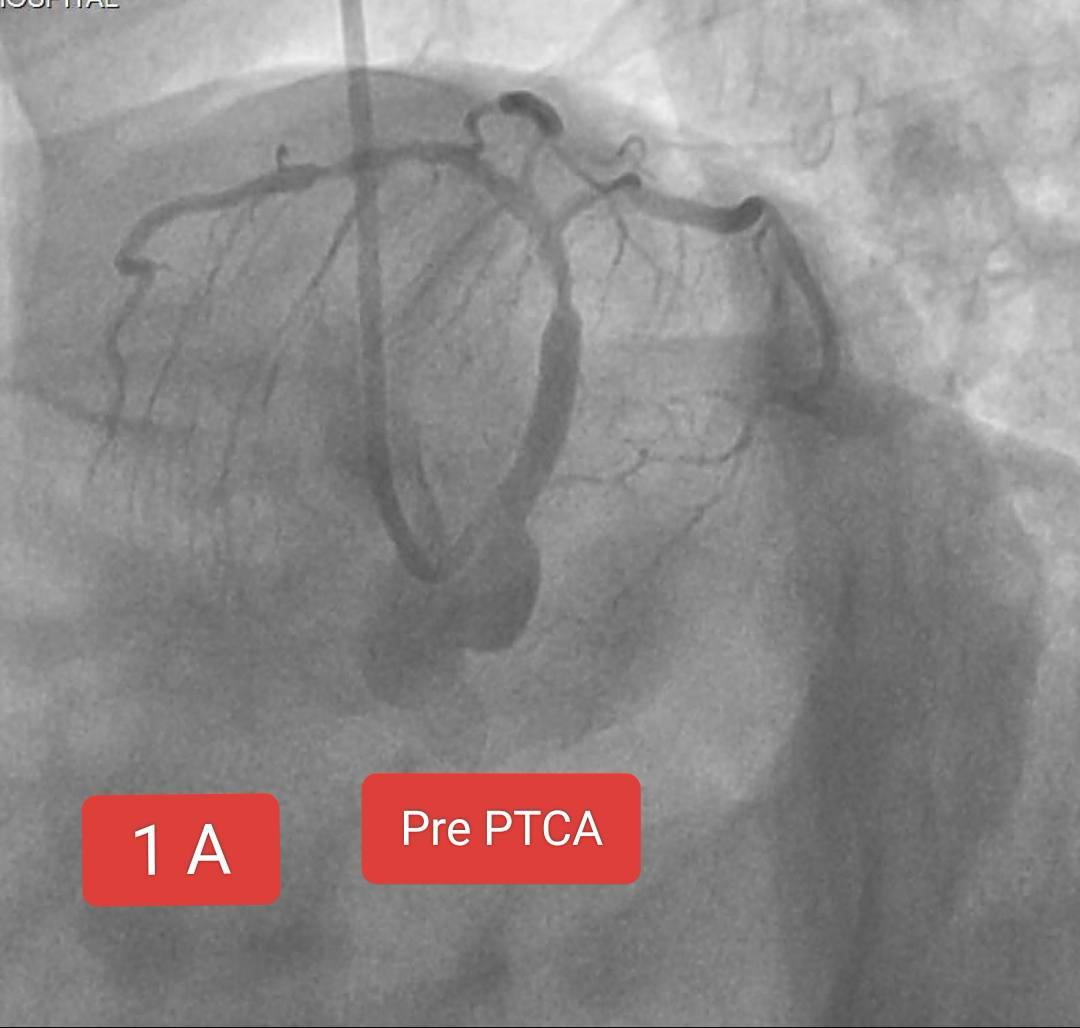

Two interesting cases of Left main stenting by mini crush technique done at Sunshine Hospital ,Bhubaneswar last month. Case 1 A 65 Years old Male Risk factors : Smoking, Hypertension Presented with Chest pain since 2 days ECG : Anterior wall STEMI ECHO : RWMA LAD Territory, LVEF 38% CAG : Left main + LAD + LCx disease PTCA done : Left main bifurcation stenting by Mini crush technique Case 1B 72 year old Male Risk factor : Smoking CAD Post PTCA status to OSTIOPROXIMAL LAD - D1 ( Bifurcation) ( 2020) Medications discontinued since 2022. ECG : aVR ST elevation ECHO : RWMA LAD Territory, LVEF : 45% CAG : Distal LMCA 95%, ostial LAD stent ISR 95% , ostial LCx 99% Patient refused CABG PTCA done : Left main bifurcation stenting by Mini crush technique Thanks to our cath lab team ( Sarfaraj Ahammed , Amit Gourav Bagh , Madhu Smita Swain , Anjan Jagannath Dash, Sanjib, Mami didi, Sameer and Raju) and Sunshine Hospital Bhubaneswar